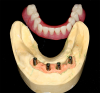

Impression copings were attached to the abutments (Figure 25); an abutment-level impression was made (Figure 26), and records were registered and sent to the laboratory for fabrication of the definitive prosthesis. A CAD/CAM all-zirconia prosthesis was planned (Figure 27, left) and fabricated by the laboratory. The prosthesis would have recesses on its intaglio surface in the location of the four anterior implants to provide space for the pickup of the attachment housings (Figure 27, right).41

Fig 27. A CAD/CAM prosthesis was planned in the planning software (left); recesses permitted pickup of the denture attachment housings of the four anterior implants (right).